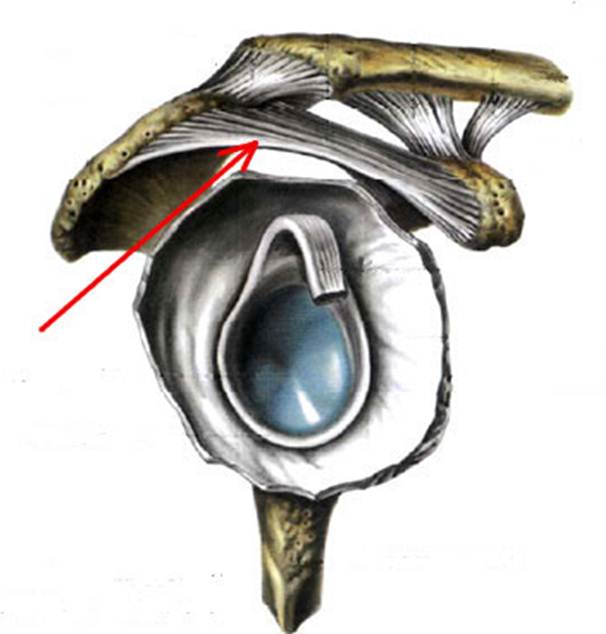

S: Стрелка указывает на art. humeri (латинский язык).

S: Стрелка указывает на lig. coracoclaviculare

S: Стрелка указывает на lig. coracoacromiale

S: Цифрой 6 обозначена суставная капсула плечевого сустава (русский язык).